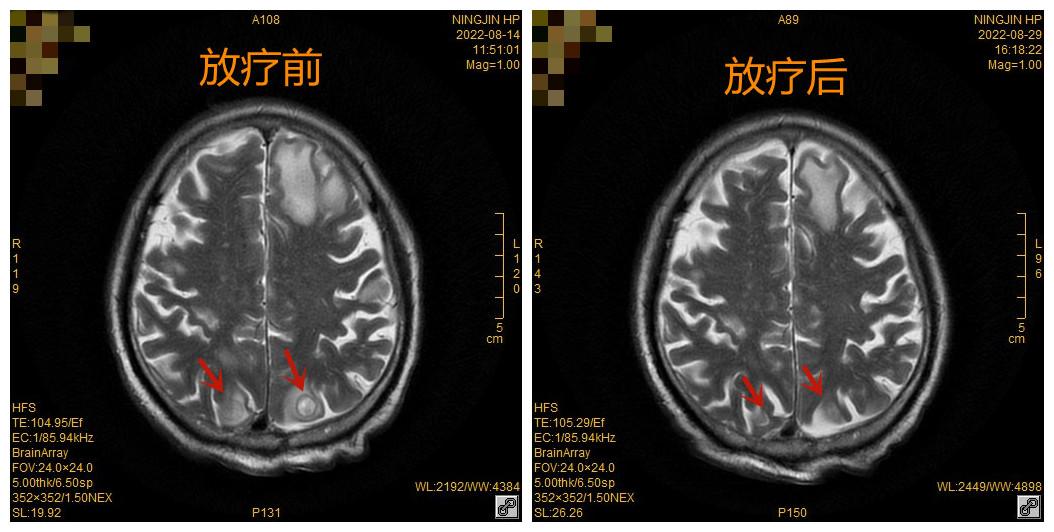

1个月前,董某某出现头痛、头晕等症状,经查头颅MRI提示:颅内多发占位病变,考虑转移瘤。

因董某某颅内存在多发转移瘤,放疗科主任赵恒西决定给予患者全脑放疗,即放疗剂量采用常规分割30Gy分10次进行,2周完成。经过放疗科团队精确定位、精确计划、精确治疗之后,患者在放疗过程中未出现特殊不适,放疗结束后复查MR颅内多发转移瘤较前均明显缩小,放疗效果明显。